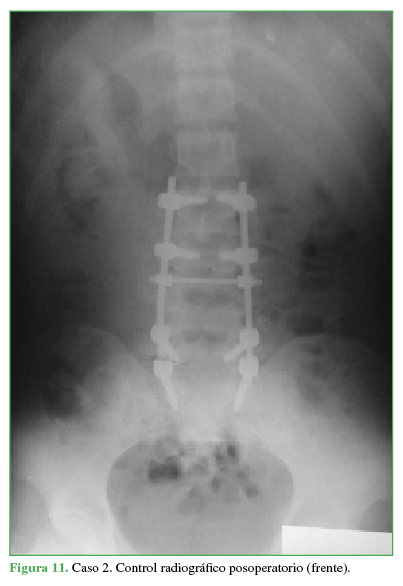

Se decide el tratamiento quirúrgico con abordaje posterior lumbosacro, reducción, descompresión posterolateral directa por técnica tipo eggshell y artrodesis lumbosacra larga L2-S1 (Figuras 11 y 12).

Control radiográfico posoperatorio (frente).

Propia

PropiaEl paciente evoluciona favorablemente, con recuperación neurológica completa. Se corrige la cifosis segmentaria con medición radiográfica a los seis meses de la cirugía adecuada (Cobb L3-L5 25°, lordosis lumbar 39°, incidencia pelviana 40°, IP-LL 1°, inclinación de la pelvis 8°).